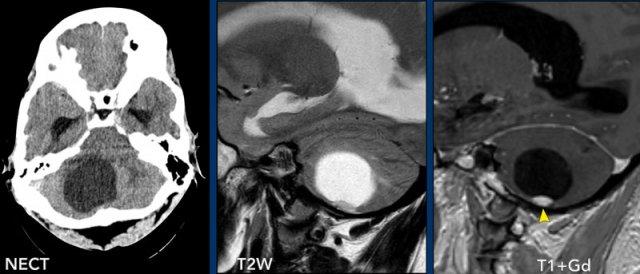

Các hình ảnh này của một trẻ 9 tuổi nhập viện vì đau đầu.

Hình ảnh

Có một khối nang lớn ở hố sau gây chèn ép và tắc nghẽn não thất bốn và thân não.

Ghi nhận một nốt đặc ngấm thuốc tương phản, cùng với sự ngấm thuốc của thành nang.

Kết luận

Chẩn đoán có khả năng nhất ở độ tuổi này là u nguyên bào thần kinh đệm lông.

Các hình ảnh này của một trẻ 3 tuổi cũng nhập viện vì đau đầu.

Có hai dấu hiệu quan trọng cần lưu ý.

Hãy quan sát kỹ các hình ảnh trước khi tiếp tục đọc.

Nang lớn có nốt ngấm thuốc ở hố sau.

Lưu ý thành nang có ngấm thuốc.

Nốt không nằm ở phía màng mềm (phần trong của màng não) khác với trường hợp u nguyên bào mạch máu.

Thành nang ngấm thuốc là một phần của khối u và cần được phẫu thuật cắt bỏ.